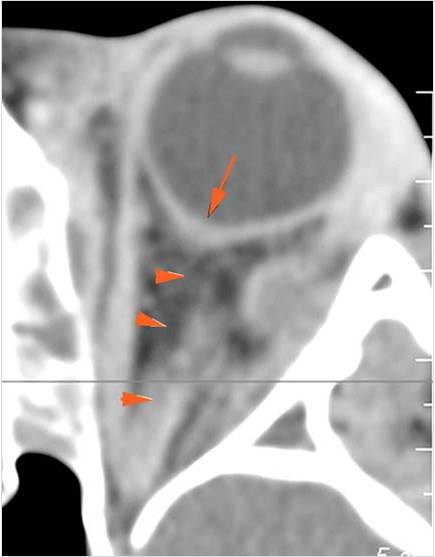

Orbits

The extraconal orbital fat is abnormal. [Yes/No]

There is a subperiosteal abscess or edema along the medial wall, roof or floor of the orbit. [Yes/No]

The extraocular muscles are swollen or otherwise abnormal. [Yes/No]

The intraconal orbital fat is infiltrated. [Yes/No]

The orbital apex and the superior and inferior orbital fissures are infiltrated. [Yes/No]

The superior and/or inferior ophthalmic veins are dilated or thrombosed. [Yes/No]

Proptosis is present. [Yes/No]

The optic nerve is stretched in appearance. [Yes/No]

The posterior aspect of the globe is tented in appearance. [Yes/No]

The uveal scleral margin of the globe is swollen or enhancing abnormally. [Yes/No]

Signs of tension orbit or endophthalmitis are present. [Yes/No]